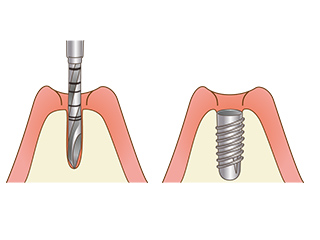

インプラントは、人工の歯根を埋め込み、人工の歯を装着することで失ってしまった歯を取り戻す治療方法です。

骨の中に穴をあけ、インプラント体を埋入する手術をします。埋入後はインプラントと骨が結合するのを待ちます。